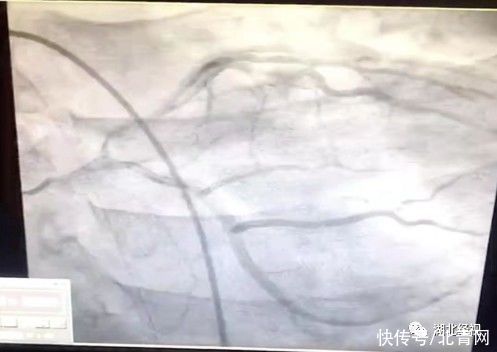

文章插圖

醫(yī)院提供圖片來源但病情剛穩(wěn)定兩天,小江又突發(fā)大面積急性心肌梗死。“心電圖反映,他的下壁、高側(cè)壁、前壁還有后壁都有梗塞,反映心肌壞死的血清心肌壞死標(biāo)記物值已經(jīng)大于50了,超過了檢驗科檢測的最高值!”醫(yī)生第一時間安排小江吃上了抗血小板、調(diào)脂穩(wěn)定斑塊的口服藥物,并聯(lián)系心內(nèi)科醫(yī)師進(jìn)行急診冠脈手術(shù)治療,手術(shù)過程順利,小江終于轉(zhuǎn)危為安。